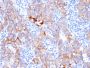

SKBR-3 cells. Breast cancer tissues.

IHC, FFPE (verified)

IHC (FFPE) (verified)

Recognizes a protein of 185 kDa, which is identified as c-erbB-2/HER-2/neu. Its epitope is localized in the extracellular domain. C-erbB-2/HER-2 is a member of the EGFR family. This MAb is specific and shows minimal cross-reaction with other members of the EGFR-family. Receptors of this family are located on the plasma membrane and consist of an extracellular ligand-binding domain that is connected to a large intracellular domain by a single transmembrane sequence. c-erbB-2/HER-2 protein is over-expressed in a variety of carcinomas especially those of breast and ovary. Primary antibodies are available purified, or with a selection of fluorescent CF® Dyes and other labels. CF® Dyes offer exceptional brightness and photostability. Note: Conjugates of blue fluorescent dyes like CF®405S and CF®405M are not recommended for detecting low abundance targets, because blue dyes have lower fluorescence and can give higher non-specific background than other dye colors.